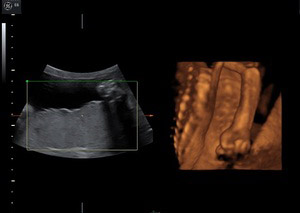

Jest jednym z najważniejszych badań w opiece perinatalnej, polegającym na dokładnej ocenie anatomii i biometrii płodu. Wykonujemy pomiary długości kości udowej – (Femur length - FL); wymiaru dwuciemieniowego główki płodu (Biparietal diameter - BPD); obwodu główki płodu (Head circumference – HC) oraz obwodu brzuszka płodu (abdominal circumference - AC). Na podstawie tych parametrów możemy ocenić prawidłowe wzrastanie oraz masę płodu.

Jest to okres najlepszej dostępności dla oceny struktur płodu w czasie życia wewnątrzmacicznego.

W czasie badania ultrasonograficznego możemy szczegółowo ocenić struktury ośrodkowego układu nerwowego, układu moczowego, pokarmowego, kostnego, a także serca, kończyn, twarzoczaszki, łożyska i płynu owodniowego.